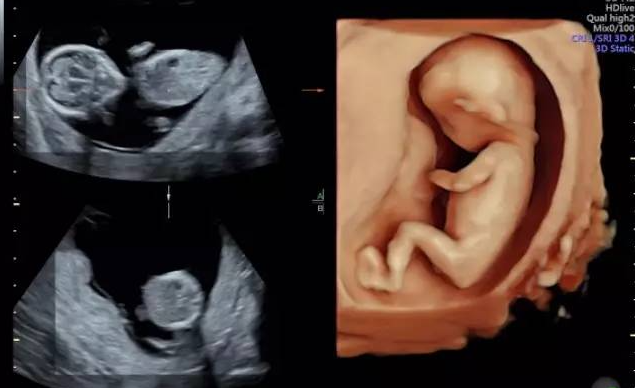

做四维彩超双胞胎为什么产检费用很贵?

简单来说,做一例双胞胎四维彩超,其工作量、技术难度、时间消耗和医生所承担的压力,都远非单胎检查的简单“翻倍”。

双重检查,耗时翻倍以上:医生需要为两个宝宝分别进行全身系统的畸形筛查,包括两个头、两个心脏、四条胳膊、四条腿等。这不仅仅是看两眼那么简单,每个胎儿都需要采集标准切面,测量数据。如果一个宝宝位置不好,等待和尝试的时间会更长。

更高的设备性能需求:为了更清晰地分辨和观察两个相互重叠的结构,医院可能需要动用更高阶的超声设备,其成本和维护费用也更高。